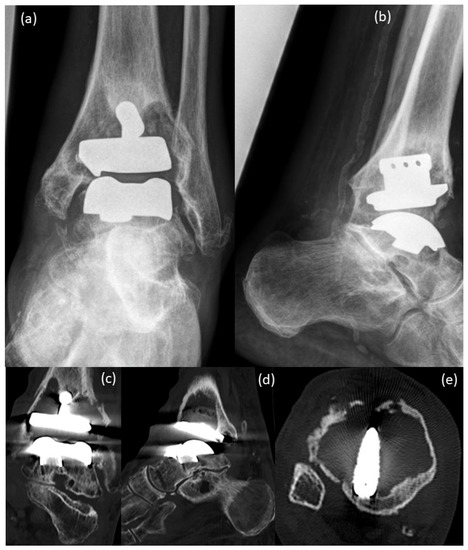

Arthrodesis and Defect Bridging of the Upper Ankle Joint with Allograft Bone Chips and Allograft Cortical Bone Screws (Shark Screw®) after Removal of the Salto-Prosthesis in a Multimorbidity Patient: A Case Report

2. Case Presentation

3. Surgical Procedure